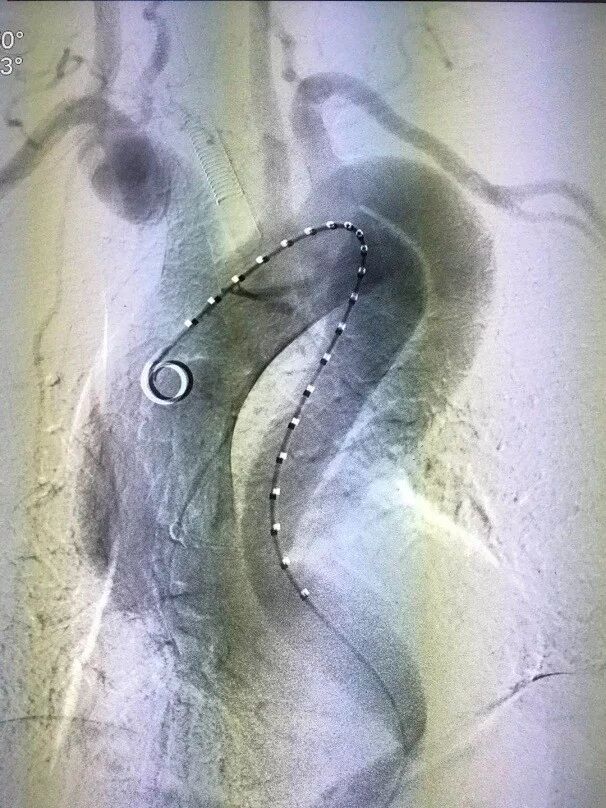

术后造影(图3、图4)和三维重建(图5、图6)显示,支架定位精准,在弓部成角很锐的复杂解剖中支架保持良好形态,基本封堵夹层破口,少量内漏术后继续观察,手术效果良好。

图5 术后三维重建-病例1

图6 术后重建-病例2